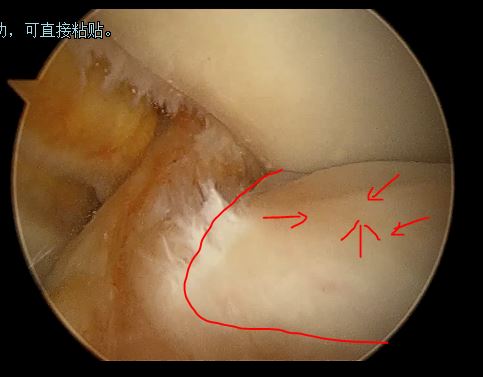

2,女性,32 岁,右膝关节反复弹响,膝关节交锁、疼痛、肿胀。

关节镜下见外侧半月板大厚, 完全覆盖胫骨平台

半月板内部分层撕裂

中央部撕裂

盘状半月板进行修整成形及缝合后

(外侧盘状半月板并撕裂,修整缝合后恢复正常的半月板形态)

(因此我们微创的关节镜技术可以修复损伤的盘状半月板)